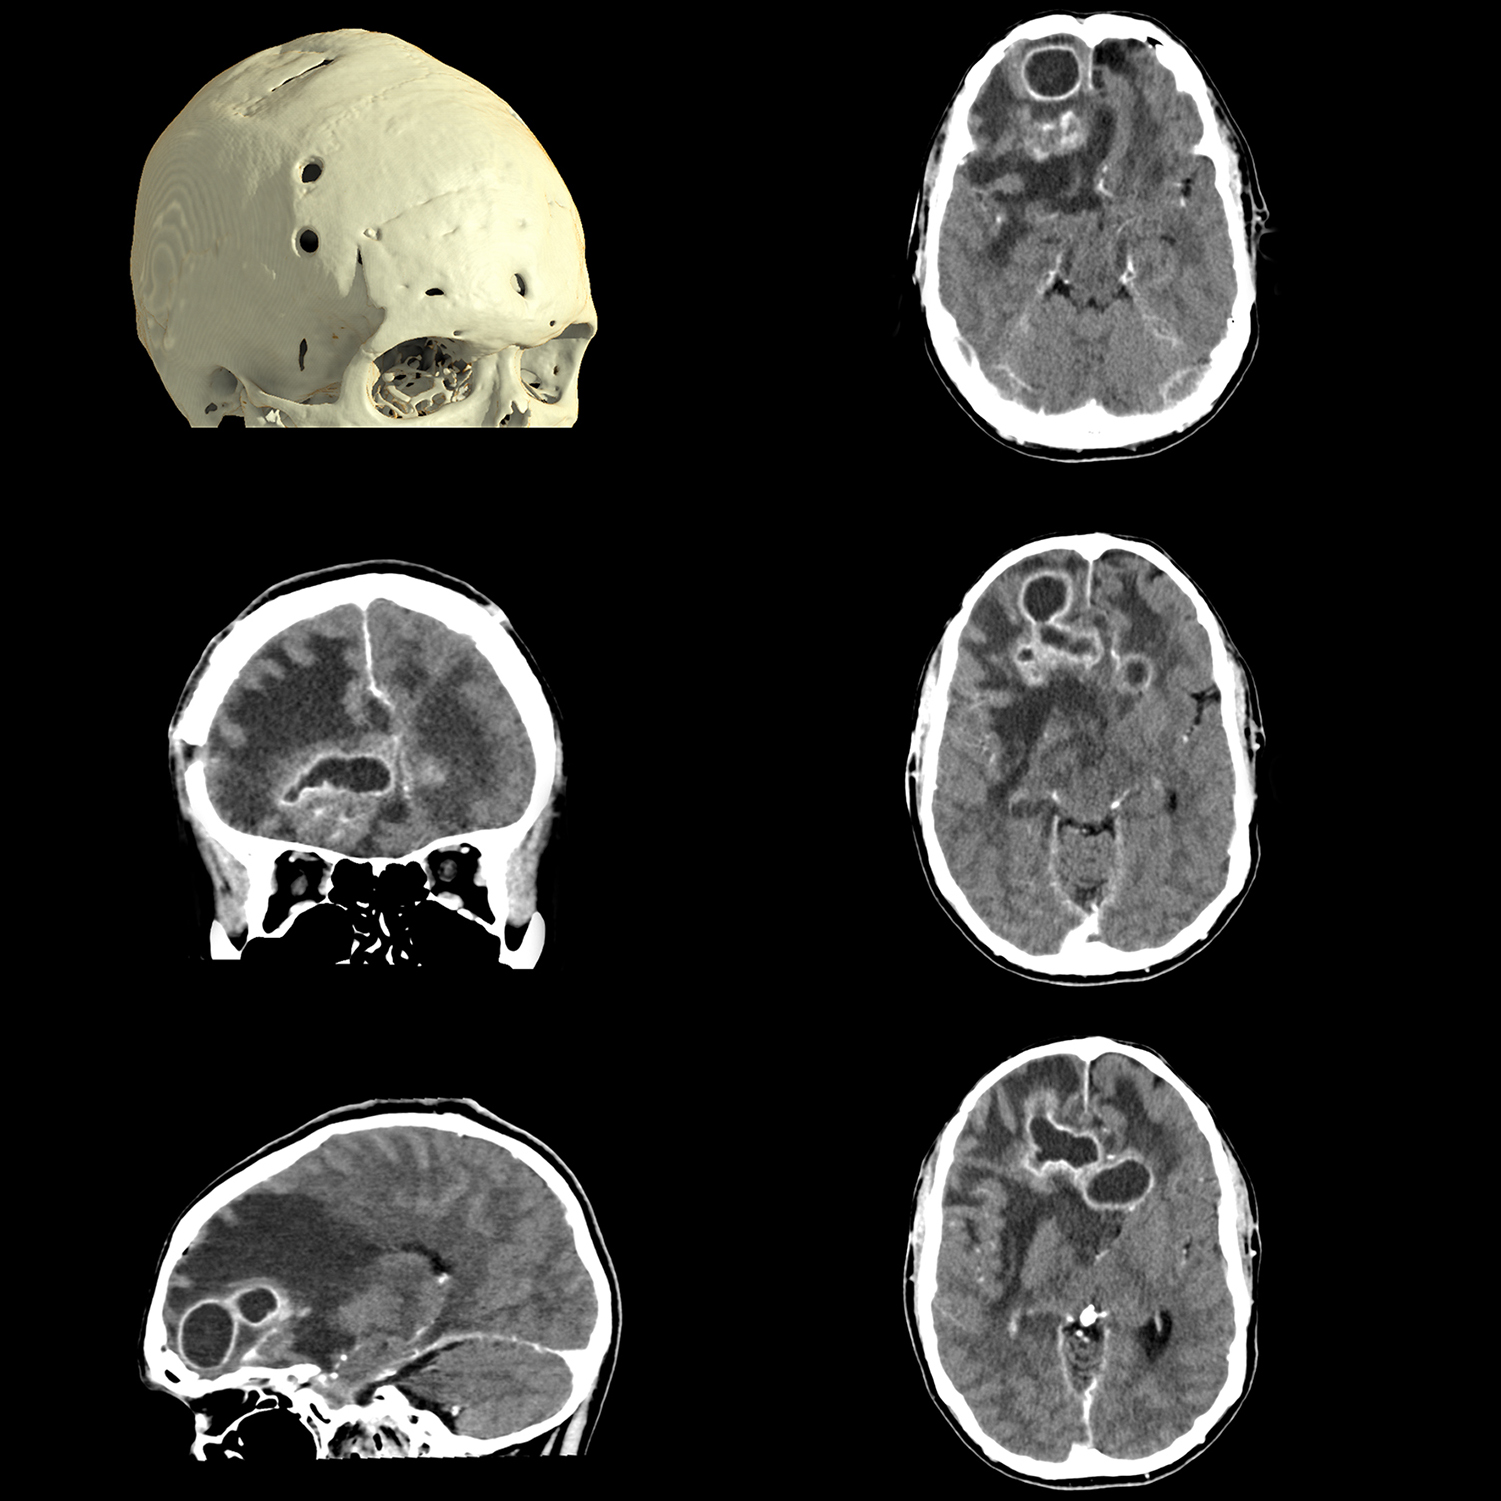

Расширенный интеллектуальный модуль Clear-IQ Engine (AiCE)

КТ-реконструкция, в которой используются инновации глубокого обучения, чтобы соответствовать пространственному разрешению и малошумным свойствам усовершенствованных итеративных реконструкций на основе моделей для получения высококачественных изображений без ущерба для скорости или дозы.

- Малый шум

- Естественная текстура изображения

- Четкое высококонтрастное разрешение

- Четкая низкоконтрастная детектируемость